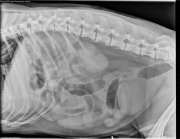

Today’s case is a 10-year-old male Portuguese Water Spaniel with anorexia. What is your radiographic diagnosis for this case?

R LAT Abdomen

The liver and spleen are normal in size and shape. The small intestine is diffusely distended with fluid with a small amount of gas. The colon is also filled with fluid. The cecum is gas distended. The peritoneal detail is good.

The findings are most consistent with functional ileus, which may be due to inflammatory disease, metabolic disease, or neurogenic disease.

• Epitheliotrophic lymphoma

Ultrasound did not identify any cause of mechanical obstruction and confirmed distended small intestine. The intestine was diffusely infiltrated with lymphoma at necropsy and was hemorrhagic in appearance. This is not a typical appearance of infiltrative disease on abdominal radiographs.